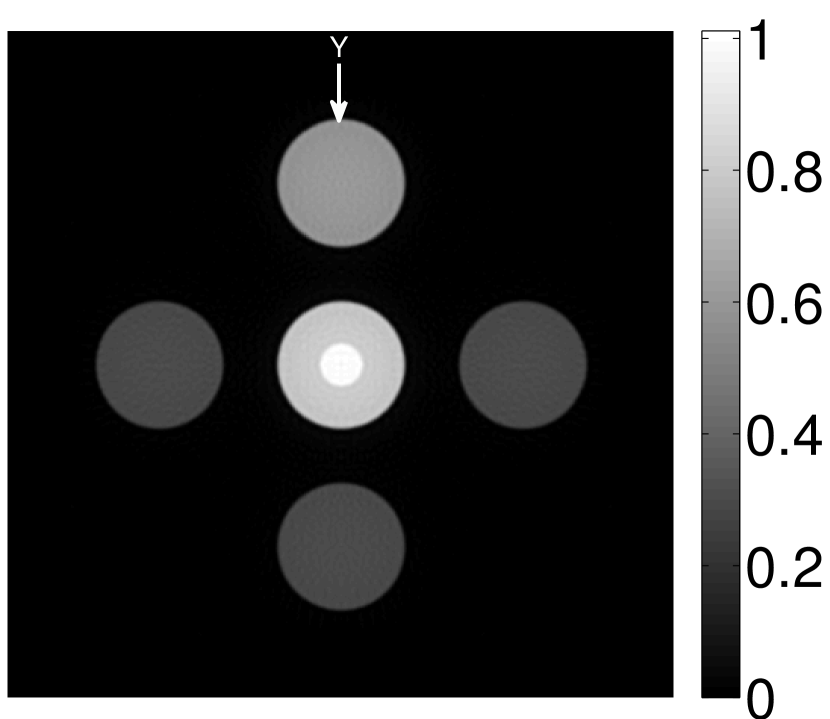

VI-E Results: kidney phantom

The images and EIRs reconstructed by use of the VP algorithm that was based on the 2D imaging model that neglected the SIR are shown in Figures 15 and 16. The latter figure contains results corresponding to different values for the regularization parameter . From Fig. 15, it can be observed that use of the conventional iterative method that utilized the measured EIR resulted in distortions and loss of details in the reconstructed images. Use of the VP algorithm improved the contrast and the details in the reconstructed images (Fig. 15(c) and 16(a)). Furthermore, the images reconstructed by use of the VP algorithm had a more uniform background.

In Figure 17, the results corresponding to use of the 3D imaging model that incorporated SIR effects are shown. The EIR estimated by the VP algorithm is also shown. In Figure 18, images and EIRs reconstructed by use of the VP algorithm with different regularization parameters values are shown.

Similar to the case described above where the transducer SIR was neglected, these results reveal that use of the VP algorithm can produce images with a cleaner background and enhanced spatial resolution than yielded by use of a conventional iterative algorithm that employed the measured EIR. For example, detailed information regarding the vessels near the organ’s periphery was better preserved by the VP algorithm than by the conventional iterative algorithm. These images corroborate our assertion that the VP algorithm can significantly reduce the artifacts and distortions in the reconstructed image. It is also worth pointing out that, unlike the numerical phantom studies, the artifacts and distortions in the images may be caused not only by the inaccurate EIR but also by other factors, such as neglecting acoustic heterogeneities and the variation of the EIRs among the elements of the transducer array. In such cases, the EIR estimated by the VP algorithm represents an effective system impulse response that minimizes the inconsistency between the measured data and the imaging model.